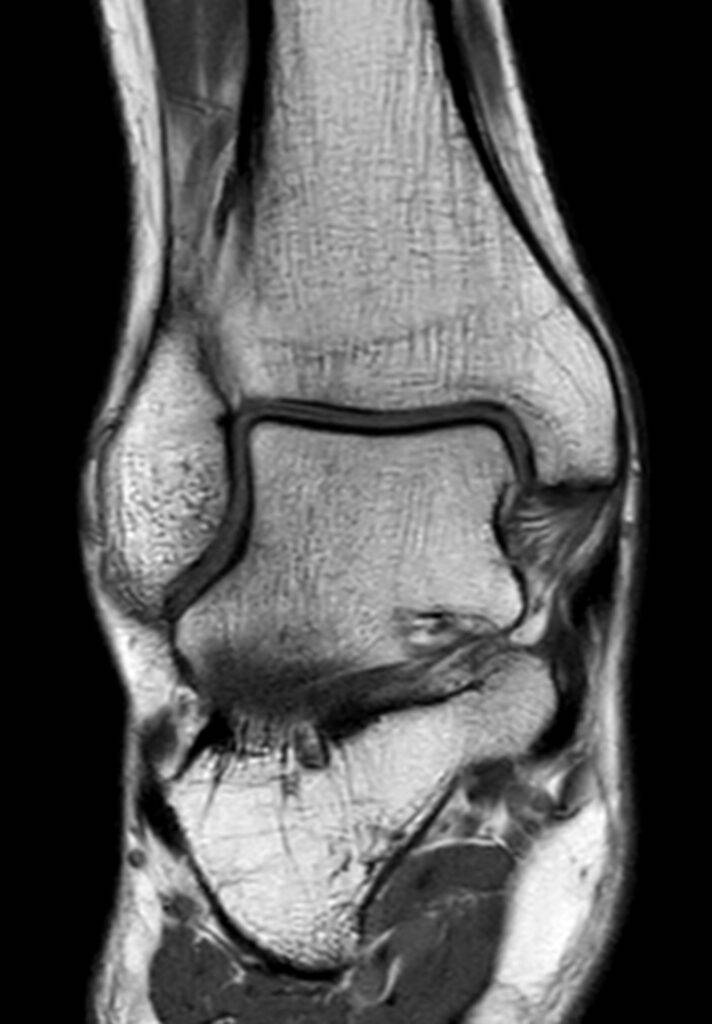

Eine Magnetresonanztomographie des Sprunggelenks, auch MRT Sprunggelenk oder MRT OSG genannt, ist ein bildgebendes Verfahren, das es ermöglicht, das Sprunggelenk mit allen Strukturen präzise und detailliert darzustellen. Die Ursache für Schmerzen oder Schwellungen im Sprunggelenk können durch eine MRT lokalisiert werden.

Das Sprunggelenk setzt sich aus verschiedenen anatomischen Strukturen zusammen, die in einer MRT dargestellt werden können. Dies geschieht durch ein starkes Magnetfeld und Radiowellen. Es werden Querschnittbilder des Sprunggelenks erstellt. Die MRT Bilder des Sprunggelenks dienen später dem Radiologen oder der Radiologin zur Diagnosestellung, damit der behandelnde Arzt oder die behandelnde Ärztin eine entsprechende Therapie ansetzen kann.

- Knochen: Knochenstrukturen, sowie das Sprunggelenk selbst werden in der MRT detailliert dargestellt. Die Unterschenkelknochen (Tibia und Fibula) sind ebenfalls sichtbar.

- Bänder und Sehnen: Das Sprunggelenk wird durch Bänder und Sehnen gestützt und stabilisiert. Kommt es zu Verletzungen oder Entzündungen an diesen Strukturen, kann dies in einer MRT dargestellt werden.

- Knorpel: Ein Teil des Gelenks bildet der Gelenksknorpel. Knorpelabnutzung oder Knorpelläsionen werden in einer MRT abgebildet.

- Weichteile: Muskeln, Faszien und Blutgefäße können ebenfalls Verletzungen erfahren. Dies äußert sich in Form von Schwellungen oder Entzündungen. Die MRT-Untersuchung ermöglicht die Lokalisierung des betroffenen Areals.